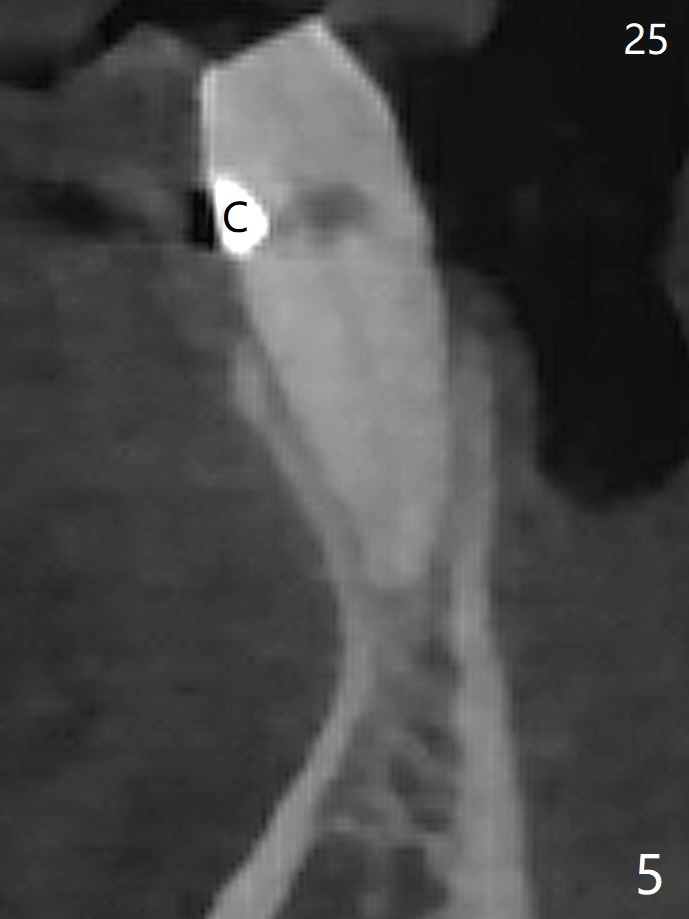

A 73-year-old woman has discomfort associated with #23 four months post Class V composite at #23-25 (Fig.1 C (*: Class V lesions)). Bone loss seems to be more severe lingually, especially at the crest (Fig.2 L). It appears that the apex of the tooth #24 is also in the large apical lesion (Fig.3). Class V composite is apparently continuous with the pulp at #25,24,23 (Fig.5-7). In contrast, Class V defect does not involve the pulp at #26 (Fig.4). If necrosis is confirmed clinically for #23 24 and 25, RCT will be conducted. Due to 7-day Amoxicillin taken for #3 implant, the patient feels that her tongue moves freely, as related to reduction in pain and swelling lingual to #23 (Fig.8 *). Endo ice test shows necrosis of #23 to 25. RCT is initiated at #23 (Fig.9) with buccal and lingual swelling. Endo may have to be at #24 with apicoectomy with PRF. The lingual swelling remains at #23, although there is no pain or purulent discharge 5 and 5.5 months post debridement (Fig.10,11). RCT is finished (Fig.12). Apicoectomy is pending with PRF. Less aggressive curettage will be done at #24 to maintain apical blood supply. Vitality tests have been done without conclusion.